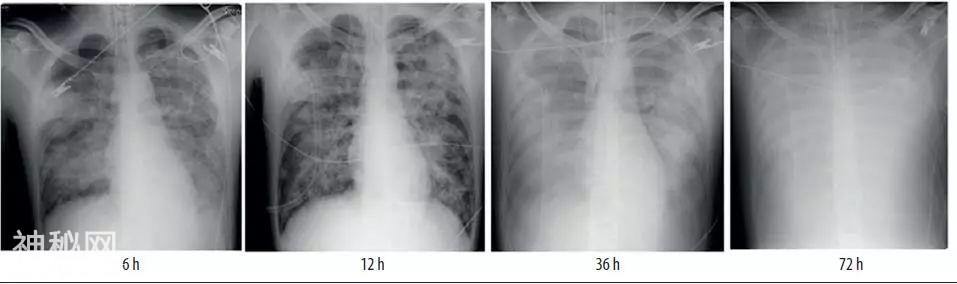

流感肺炎进展快,金葡菌肺炎进展也很快,假如流感合并金葡菌,会肿么样?比小李飞刀还快!

下面就是流感合并金葡菌肺炎的胸片,静静地感受一下!

教你从肺CT上分辨是哪种细菌感染丨葡萄球菌肺炎篇-6.jpg

并且,这是甲氧西林敏感的金葡菌。